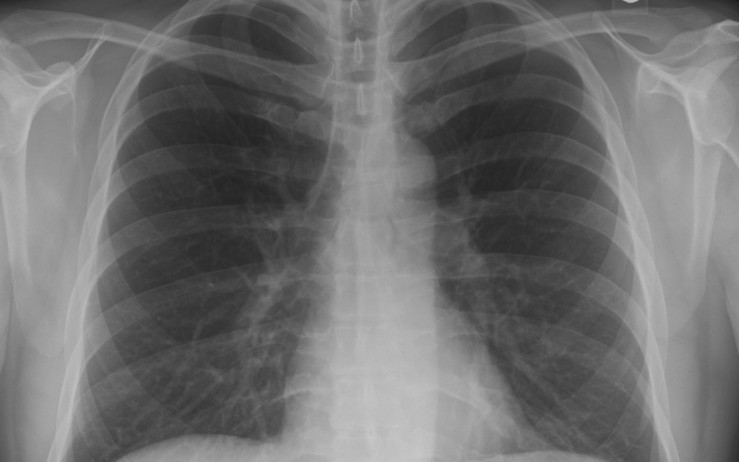

This is another post on Spring Boot that will show how to build a sample web application using Deep Java Library (DJL), an open-source Deep Learning library for Java to diagnose COVID-19 on X-ray images.

The sample app is a Spring Boot based version of DJL's similar COVID-19 example and it has a simple static HTML page built using Twitter Bootstrap and JQuery where users can submit an image URL to a REST api where the DJL library will download the image and predict if it's an X-ray image of lungs infected with COVID-19 or not.

Disclaimer: This is only a demo application based on the dataset at https://github.com/ieee8023/covid-chestxray-dataset and it SHOULD NOT be used for actual medical diagnosis.